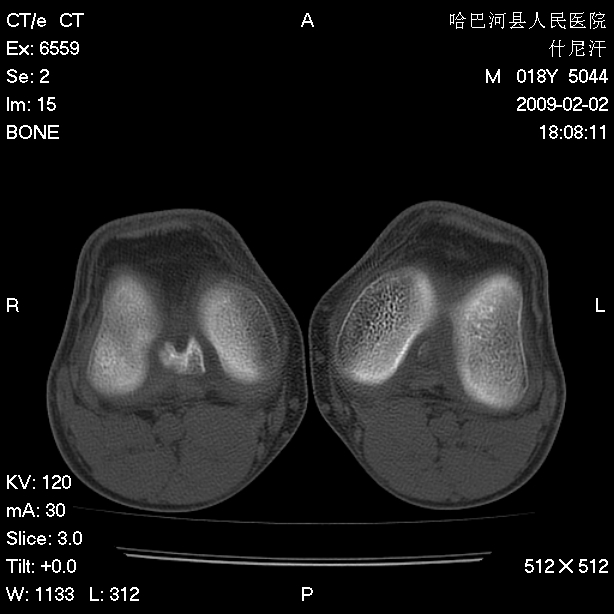

标题: CT17889:外伤后右膝关节反复疼痛3年余 [打印本页]

标题: CT17889:外伤后右膝关节反复疼痛3年余

ct未见明显异常。关节腔未见明显积液,半月板未见明显撕裂。但最好还是mri看看韧带及半月板情况。